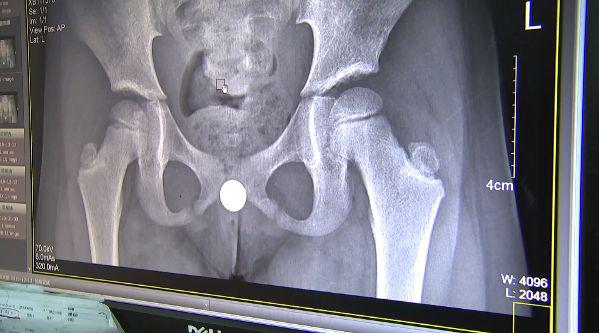

2019 年年初,浙大儿院专家从一个 11 岁小男孩的膀胱里,取出 70 颗磁力珠,是通过尿道塞进去的。11 岁男孩突然感觉肚子痛得厉害,爸妈见状,连夜带着他到浙大儿院就诊,最终在膀胱里取出 70 颗磁力珠。